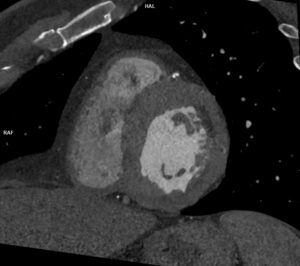

Video 5: achiziție IRM axială cu protocol de perete vascular regiune cervicală

Este cazul unei paciente de 24 de ani cu un părinte cunoscut cu Sd Alagille care se prezinta la camera de gardă pentru cefalalgii importante. Examinarea angioCT a evidentiat ocluzie de artera carotidă internă stângă la origine şi a fost completată cu examinare IRM pentru diagnostic diferențial cu disecție de perete vascular.